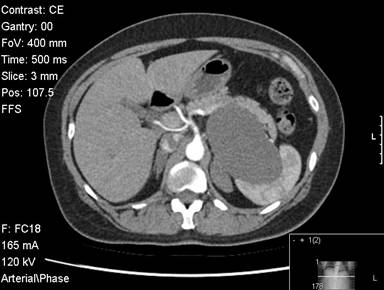

A fifty-two-year-old female was evaluated for abdominal pain. She had a vague history of upper and left sided abdominal pain for 6 months. An ultrasound showed a cystic lesion in the left upper abdomen. A CT scan subsequently confirmed the presence of a large 10 cm cystic lesion in very close proximity to the spleen and the pancreas. The lesion reached close to the neck of the pancreas. The lesion involved the mid-body / tail of the pancreas, was abutting against the spleen (Figures 1 and 2). There was close proximity to the splenic vein, although the vein was patent. The splenic artery was close but seemed uninvolved (Figure 3). The cyst wall was uniform. There were no internal septations or any other features to suggest an intracystic solid component or bleeding. There were no calcifications with the cyst. The rest of the pancreas appeared normal with no evidence of pancreatitis. There were no gall stones or any other biliary abnormality. Clinicoradiologically it was felt to be a large cyst possibly a splenic cyst. However given the fact that she was symptomatic, we decided to proceed with a laparoscopic resection. All her blood tests including tumour marker profile (CA 19-9 and CEA) were normal. She underwent a laparoscopic distal pancreatectomy with splenectomy. At laparoscopy we discovered a large cystic lesion occupying the lesser sac and abutting against the spleen. The pancreas could not be separated off the cyst. We completely mobilised the stomach off the cyst and the pancreas, to completely expose the pancreas with the cyst in the lesser sac. We completed a distal pancreatectomy with splenectomy laparoscopically, with complete enbloc excision of the cyst (Figure 4). Post-operative recovery was uneventful and the patient was discharged 4 days following surgery. Gross pathology showed a 90x50x60 mm cystic lesion, attached to and arising from the inferior and posterior aspect of the pancreas. On pathology the rest of the pancreas appeared normal and the splenic capsule was not breached. The histology of the cyst showed the presence of pseudo stratified ciliated columnar epithelium , overlying some connective tissue (Figure 5; H&E, magnification x10) .Similar features were confirmed on the high powered images of the cyst wall as well (H&E, magnification x20). Based on these characteristic and rather unusual histological features, the diagnosis of a ciliated foregut cyst of the pancreas was established.

Figure 1. CT scan image showing the cyst within the body/tail of the pancreas. |